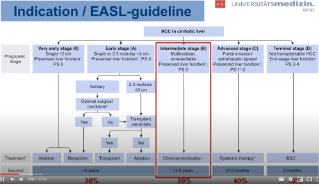

DEB-TACE with DC Bead - Clinical considerations - Dr Roman Kloeckner

Second of three podcasts on DEB-TACE with DC Bead Dr Roman Kloeckner will discuss 1) Indications for TACE - stage migration, at minute 0:27 2) Pre-, intra- and postinterventional imaging, at minute 1:42 3) Cases TACE vs SIRT, at minute 5:55